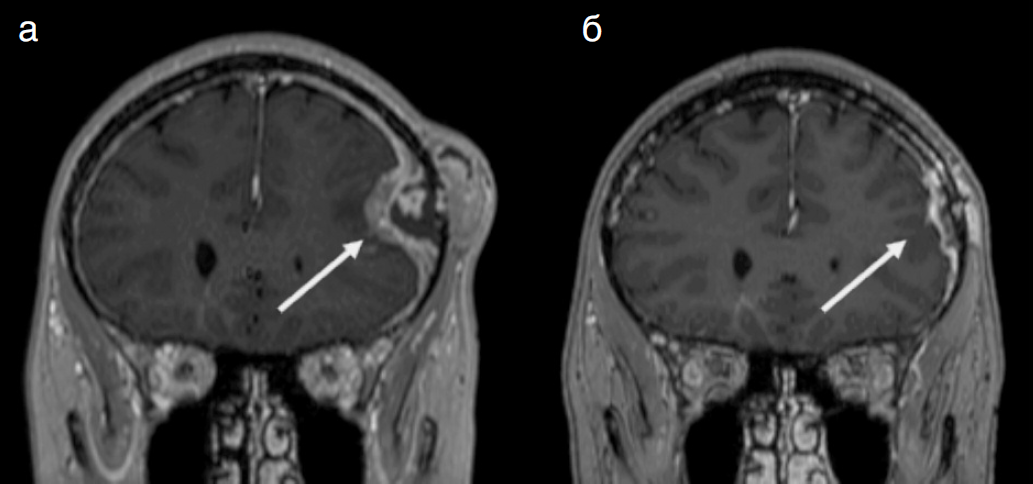

In February 2019, the MRI revealed the frontal bone affection, with subcutaneous permeation to the depth of 1.1 cm and intracranial permeation to 2.1 cm – the mass lesion with signs of diffusion restriction, with the dimension of up to 3.5×3.8×3.8 cm. A similar formation was identified in the left frontal pole with the dimension of 2.2×2.0×2.15 cm and in the right frontal bone of up to 1.1×1.5 cm, as well as the inhomogeneous MR signal locus in the right parietal bone up to 0.8 cm in diameter. The lesion of cerebral membranes of up to 6.2 cm long and 1.4 cm thick was noted (Fig. 2).

Eribulin therapy (2nd L of chemotherapy) started since February 2019 in dose – 1.4 mg/m2 on days 1, 8 days of the 21-day cycle + bisphosphonates infusion, 10 cycles in total. The effect was partial respone (decrease in the intracranial lesions) and stabilization in the bone lesions and mediastinal lymph nodes; Fig. 2. The duration of the response was 8 months, a significant improvement in the quality of life was noted. The tolerance of chemotherapy with eribulin was satisfactory, neutropenia grade 1–2 and anemia grade 1 were noted. No dose reduction was required.

Fig. 2. Metastases in the frontal bone, cerebral membranes with intracranial component (a – before the eribulin therapy, b – after 10 cycles of eribulin).

Рис. 2. Метастатическое поражение лобной кости, мозговых оболочек с интракраниальным компонентом: а – до лечения эрибулином;

б – после 10 введений эрибулина.